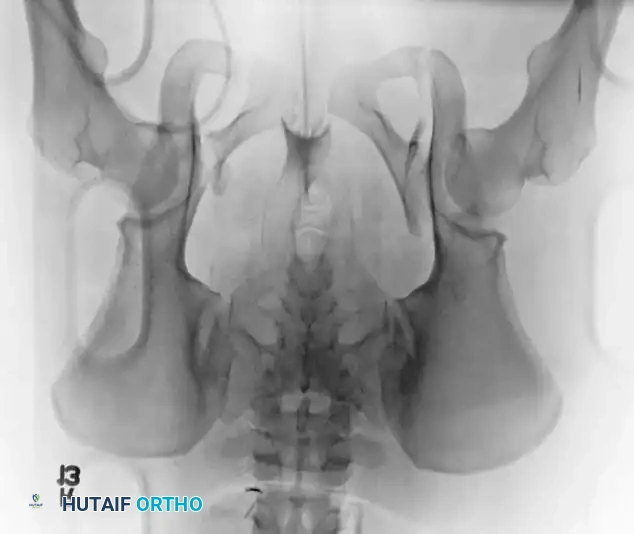

Radiographic Evaluation

Standard evaluation begins with an Anteroposterior (AP) pelvis radiograph. However, definitive surgical planning requires specialized views and advanced imaging.

• Inlet View: Directed 45 degrees caudad. Best evaluates anterior-posterior translation, internal/external rotation, and sacral impaction.

• Outlet View: Directed 45 degrees cephalad. Best evaluates vertical translation and sacral foraminal anatomy.

• CT Scan: The gold standard for evaluating posterior ring injuries, sacral dysmorphism, and preoperative planning for percutaneous fixation.

Image